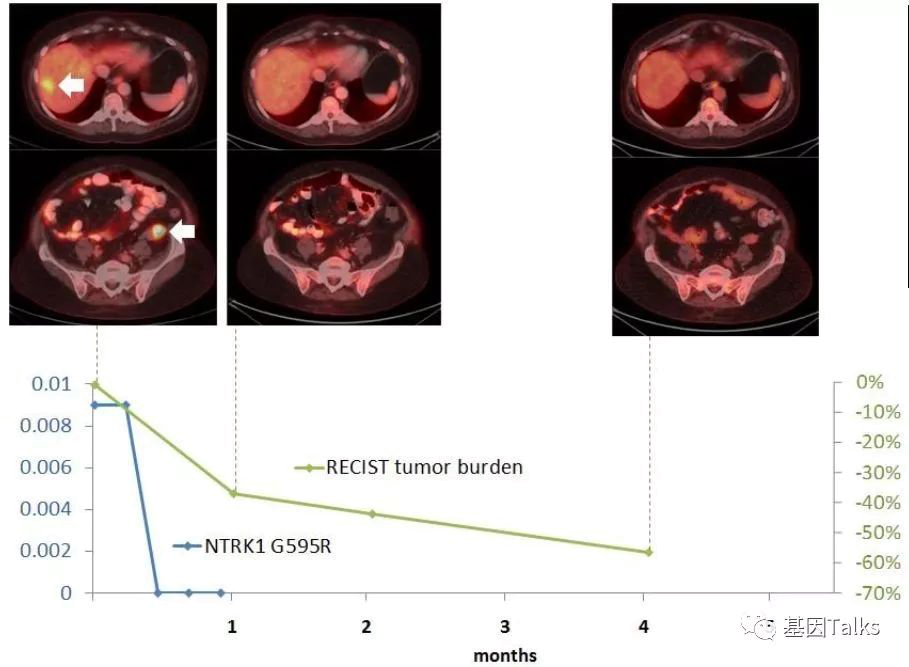

科学家经过研究发现,拉罗替尼的耐药机理和EGFR情况类似,主要是靶点本身(NTRK基因)产生了新的突变,比如TRKA出现G595R突变,TRKB出现 G639R 突变或者TRKC出现G623R突变。根据这些发现,第二代TRK靶向药物LOXO-195已经出炉,专门来对抗耐药的新突变。

上图上半部分,这位耐药患者尝试LOXO-195新药后,肿瘤再次快速缩小,用药4周后,肿瘤负担减少了38%,继续治疗显示肿瘤负担减少了58%。

上图下半部分显示治疗2周后,新发的耐药突变位点G595R已经检测不到,到现在治疗已经6个月了,治疗效果依然很好,未见有新的耐药位点出现。LOXO-195已经被FDA批准正式召开临床试验,耐药患者有了新希望。